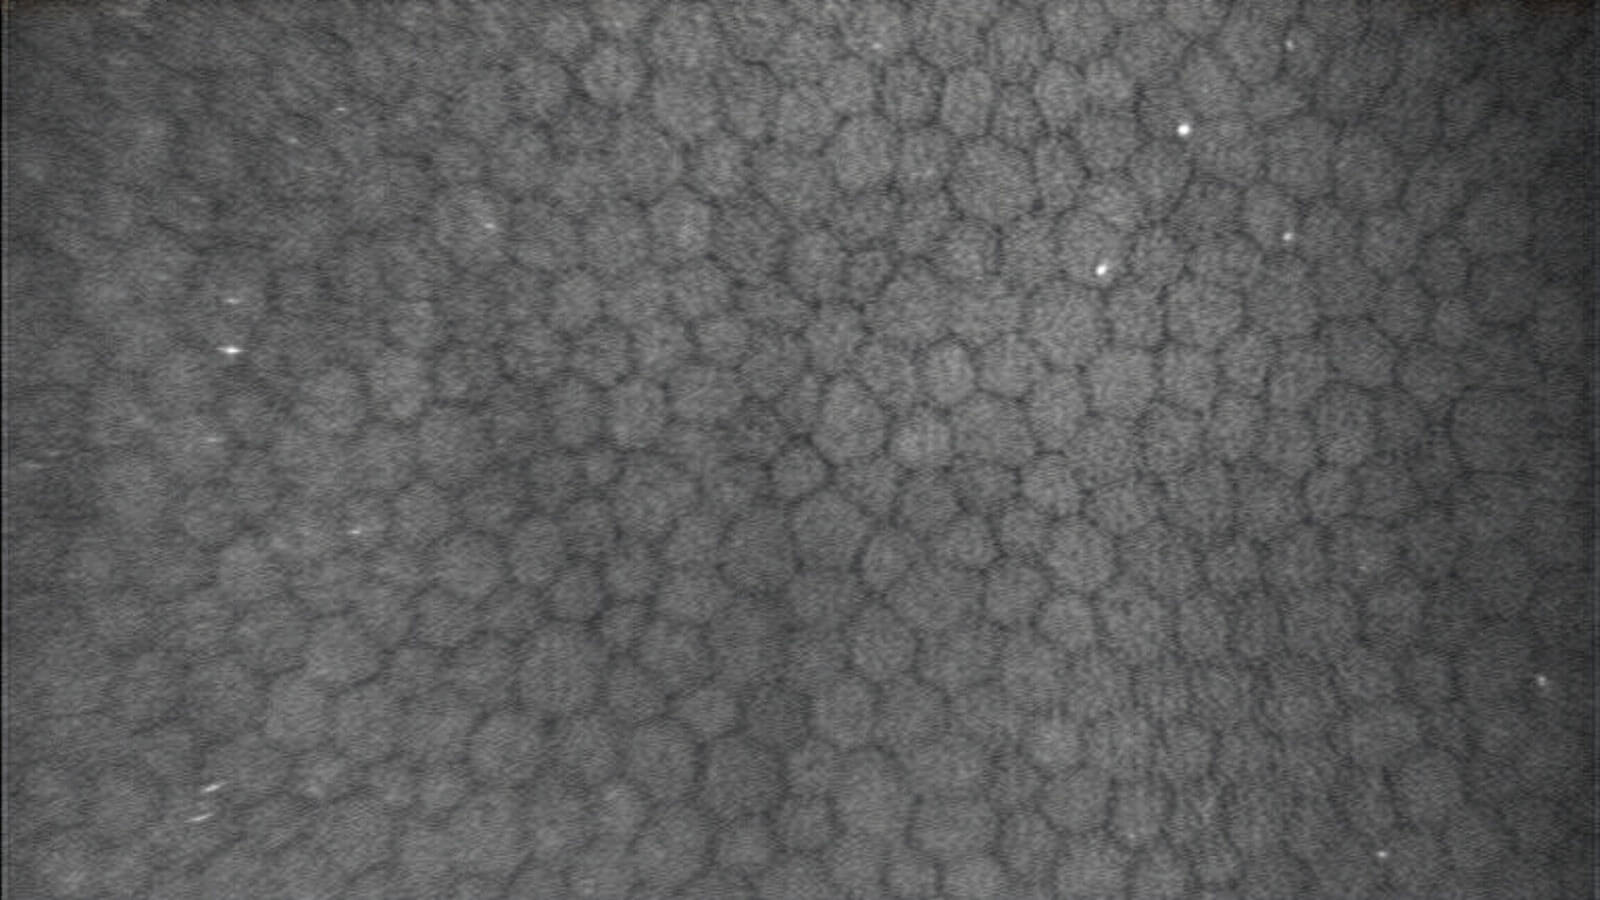

- Corneal endothelial cell density and morphology

- Confocal image analysis

In partnership with Case Western Reserve University’s Department of Biomedical Engineering, CIARC is advancing machine learning applications that move beyond traditional imaging software to transform lid, cornea and anterior segment image analysis. Current projects focus on developing AI-driven algorithms for the automated assessment of endothelial cell density and morphology of the donor cornea endothelium, as well as guttae in Fuchs endothelial corneal dystrophy. The CIARC in conjunction with Case Western Reserve University’s Department of Biomedical Engineering and the Eversight Eye Bank recently was awarded a High Impact grant from the Eye Bank Association of America to advance this work for the donor corneal endothelium.

In addition, CIARC researchers are using AI-based analysis of specular microscopy images to more precisely and objectively track the progression of Fuchs endothelial corneal dystrophy, with particular focus on the quantification of guttae and endothelial cell morphology.